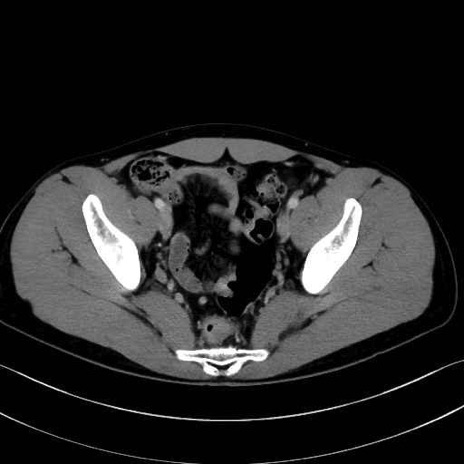

2. 腸腰筋群と骨盤底筋

大腰筋 (Psoas major)

腸骨筋 (Iliacus)